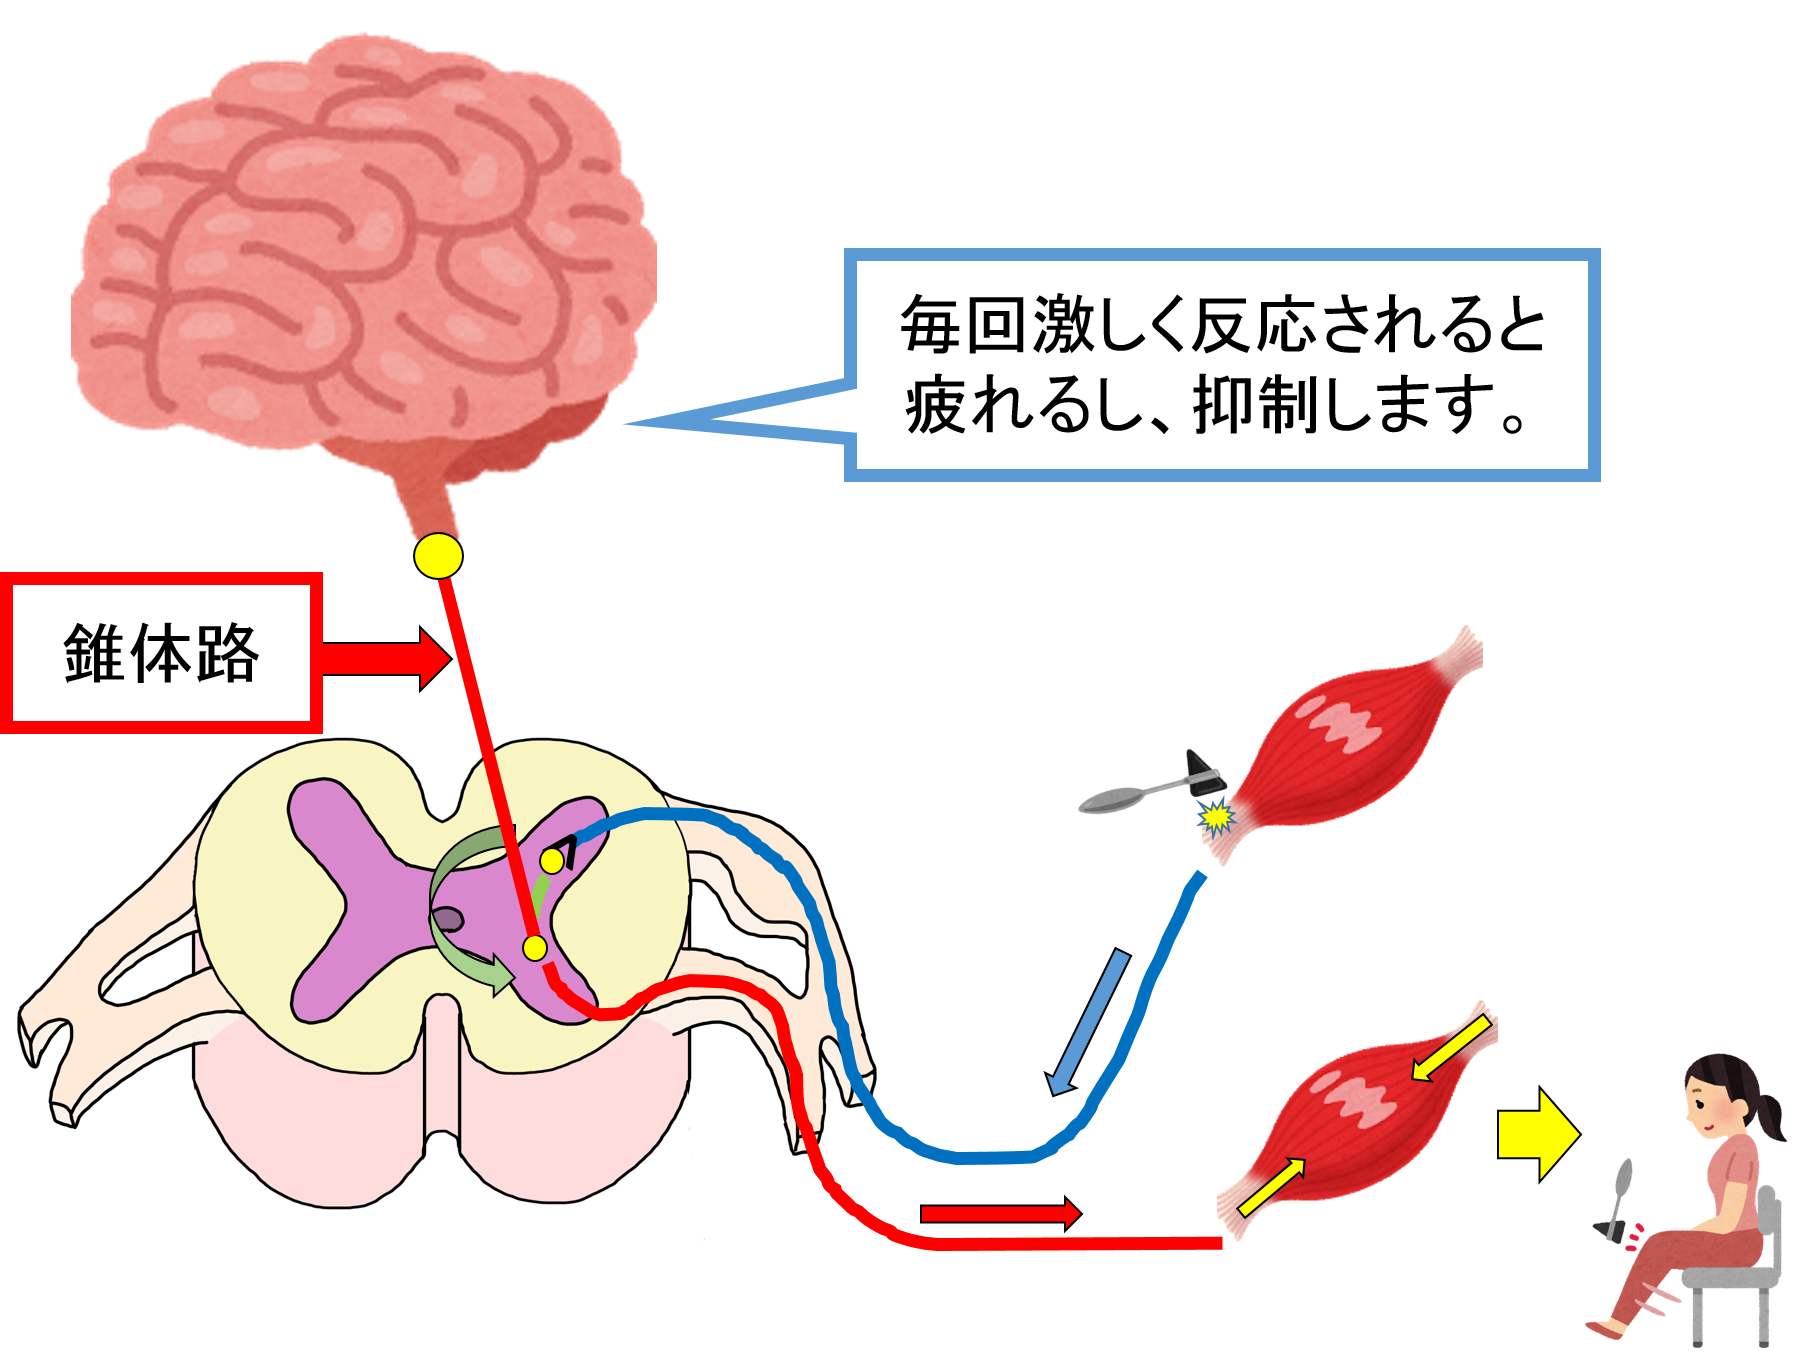

深部腱反射を評価する意義 目的とは 表記方法から実際の方法まで 白衣のドカタ

皮質脊髄路 錐体路 を脳画像から簡単に見つける方法 運動麻痺を理解する5つの見るべきポイントとは リハアイデア

錐体路とは イラストを用いて説明します リハビリの引き出し